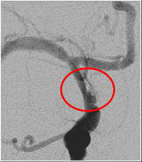

此時右半邊大腦處於嚴重缺血的狀態,若無法即時將血管打通,將會有大範圍中風的情況產生,過去的文獻報導這類的患者死亡率可以高達51%,在集合本院小兒神經科專家與腦中風中心神經放射線科專家共同會診評估後,建議積極使用血管內介入性治療,打通腦部阻塞的血管。醫療團隊將一條微細的導管穿過狹窄的內頸動脈,深入患者右側中大腦動脈,在6小時的黃金時間內,成功將中大腦動脈的血栓溶解,並將原先內頸動脈剝離而狹窄的血管,利用囊球擴張與支架置放,重建血管使其恢復原有的管徑大小,患者出院時除了手部細微動作受到影響外,看不出身體活動有中風過的症狀,目前追蹤已將近一年,無中風再發的情形。

囊球成形術圖,右邊圖是囊球撐開後剝離的血管內皮依舊存在